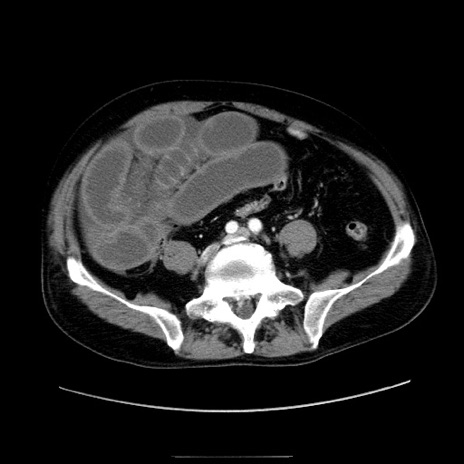

症例30(横断像)

【症例】80歳代男性

【主訴】臍周囲痛

【現病歴】約6時間前から臍下部痛が出現。次第に腹部膨隆・背部痛も生じてきたため来院。背部痛の場所は変化しない。

【身体所見】意識清明、BT 36.3℃、BP  131/87mmHg、P 87bpm、SpO2 100%(RA)、臍周囲自発痛・圧痛あり、反跳痛なし、自発痛部位に一致して板状硬あり、腹部膨隆、腸雑音減弱、CVA tenderness両側陰性。

【データ】WBC 19600、CRP 0.33